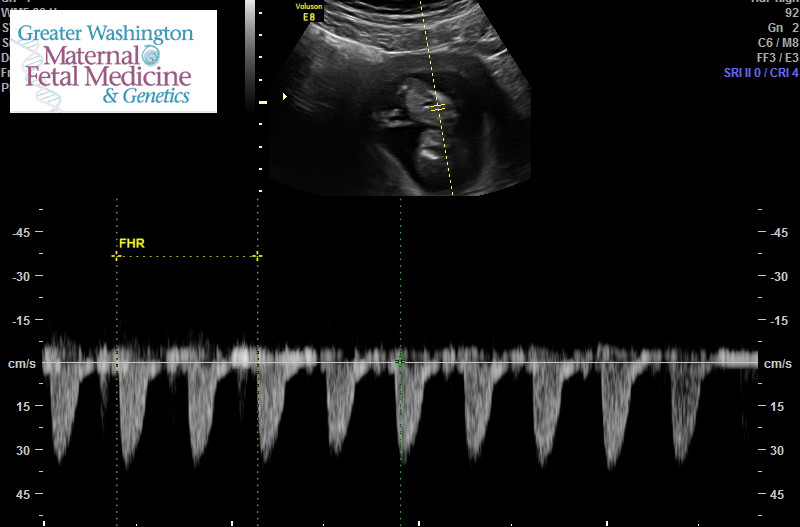

I was 9 weeks, obgyn asked for an ultrasound since I only had one at 5 weeks and it was a empty sac. Such a relief since I read to much into things. Heartbeat was 164. It was kicking and flipping on its head. I teared up since my last pregnancy ended as an ectopic. * that is a foot not a peepee ☺️